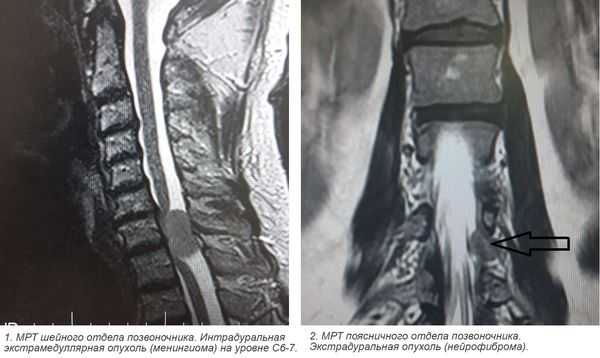

Наиболее безопасным и эффективным способом, позволяющим диагностировать опухоль спинного мозга, выступает МРТ позвоночника. Метод дает возможность послойно визуализировать расположенные в позвоночном столбе мягкотканные образования, проанализировать объем и распространенность опухоли, ее локализацию по отношению к веществу, оболочкам и корешкам спинного мозга, сделать предварительную оценку гистоструктуры новообразования.

Экстрамедуллярные опухоли — спинальные новообразования, не прорастающие в спинной мозг, а локализующиеся около него. Могут располагаться над и под твердой мозговой оболочкой. Обычно экстрамедуллярные опухоли начинаются с признаков поражения спинального корешка, потом происходит сдавление спинного мозга с поражением половины, а затем всего его поперечника. Скорость развития клиники зависит от вида опухоли. В диагностике наиболее информативна МРТ, при невозможности её проведения — КТ-миелография. Лечение хирургическое — радикальное удаление. В случае злокачественных новообразований проводится химио- и радиотерапия.

В зависимости от расположения экстрамедуллярные опухоли разделяют на шейные, грудные, пояснично-крестцовые и опухоли конского хвоста. По отношению к твердой оболочке спинного мозга в клинической неврологии различают субдуральные (интрадуральные) и эпидуральные новообразования. У взрослых первые составляют до 65% спинномозговых опухолей, а вторые — 15%.

Виды экстрамедуллярных опухолей

- Менингиома— опухоль мягкой оболочки До 70% случаев связано с расположением в грудном отделе, около 20% - в шейном. Возникает субдурально, но в 10-15% имеет эпидуральную составляющую. В 2 раза чаще встречаются у женщин, что связывают с влиянием на их рост женских гормонов.

- Нейрофиброма — чаще поражает чувствительные (сенсорные) корешки. Диффузно прорастает спинальный корешок, вызывая его утолщение. Поэтому её удаление возможно только путем полного пересечения корешка. Нейрофиброма может трансформироваться в злокачественную нейрофибросаркому. Риск малигнизации повышен у пациентов с нейрофиброматозом.

- Томография. Наиболее достоверным методом, визуализирующим экстрамедуллярные опухоли является МРТ позвоночника. Она дает возможность определить точное расположение, распространенность, форму опухоли, предположить ее вид, оценить степень спинальной компрессии. При наличии противопоказаний к МРТ альтернативным методом выступает КТ-миелография.

3. Магнитно-резонансная томография (МРТ) с контрастным усилением. На данный момент это основной метод диагностики новообразований спинного мозга. МРТ позволяет визуализировать весь спинной мозг и позвоночник и определить локализацию опухоли. Накопление контрастного вещества определяет не только распространение, но и гистологическую структуру опухоли [5] [6] .